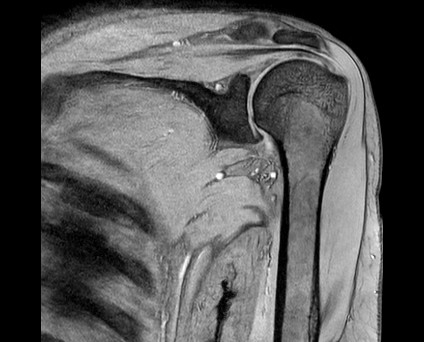

整形領域の撮影

当センターでは、体幹部のみならず四肢の撮影も行っております。膝関節、肩関節、手関節、足関節など整形領域の撮影も行っております。最新のAI技術を用いることで、より細かく描出できるようになり、靭帯損傷や骨折、筋損傷を見つけることが出来ます。

『肩関節MRI画像』